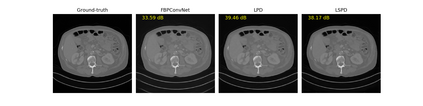

We propose a new type of efficient deep-unrolling networks for solving imaging inverse problems. Conventional deep-unrolling methods require full forward operator and its adjoint across each layer, and hence can be significantly more expensive computationally as compared with other end-to-end methods that are based on post-processing of model-based reconstructions, especially for 3D image reconstruction tasks. We develop a stochastic (ordered-subsets) variant of the classical learned primal-dual (LPD), which is a state-of-the-art unrolling network for tomographic image reconstruction. The proposed learned stochastic primal-dual (LSPD) network only uses subsets of the forward and adjoint operators and offers considerable computational efficiency. We provide theoretical analysis of a special case of our LSPD framework, suggesting that it has the potential to achieve image reconstruction quality competitive with the full-batch LPD while requiring only a fraction of the computation. The numerical results for two different X-ray computed tomography (CT) imaging tasks (namely, low-dose and sparse-view CT) corroborate this theoretical finding, demonstrating the promise of LSPD networks for large-scale imaging problems.